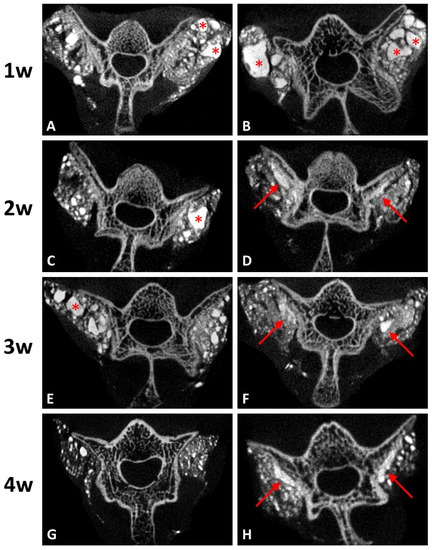

3.3.2. Reduced Effect of Residual Graft Ratio on DCP-Rich CPC by Integrating Collagen

Coronal micro-CT images at every stage in both groups are presented in Figure 5. At the first post-operative week, both groups had irregular shape of radiopaque lobules, which indicated the residual grafts (Figure 5A,B). After two weeks, micro-CT imaging of the group with DCP-rich CPC supplemented with 0.4 mL collagen showed that the radiopaque lobules became smaller and closer to the transverse process and lamina (Figure 5D,F). At the fourth post-operative week, the band-like callus formation with similar radiodensity to nearby spine structure was noted along the vertebra surface (Figure 5H). However, the same results were not observed in the group with DCP-rich CPC only. The radiopaque lobules remained scattered irregularly until the third week (Figure 5C,E). Although the residual grafts were absorbed slowly after four weeks, no band-like callus formation was noted (Figure 5G).

Residual graft volume of both sides was measured through the contrast of the image in Figure 5. The residual graft ratio was significantly different between the control group and the DCP-rich CPC supplemented with 0.4 mL collagen group at three and four weeks after implantation (Figure 6). Notably, the residual graft ratio of the DCP-rich CPC supplemented with 0.4 mL collagen group was reduced to 55% at three weeks and 30% at four weeks. Meanwhile in the control group, the residual graft ratio was 70% at three weeks and 50% at four weeks. The residual graft ratio in the DCP-rich CPC supplemented with 0.4 mL collagen group was significantly lower than that in the collagen-free DCP-rich CPC group at both three and four weeks postoperatively (p < 0.01).

Figure 5. Coronal micro-CT images of the lumbar spines. (A,C,E,G) represent post-operative 1–4 weeks of DCP-rich CPC only, respectively. (B,D,F,H) represented post-operative 1–4 weeks of the DCP-rich CPC supplemented with 0.4 mL collagen, respectively. The star symbols indicate residual grafts and the arrows indicate callus formation.